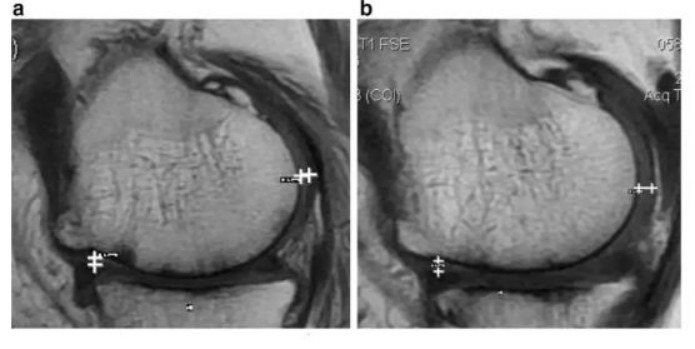

·研究结果:关节内注射骨髓间充质干细胞6个月后,,疼痛、、、、功能状态和步行距离均提高。。6名治疗组中3名患者在治疗前后的MRI比较可以看出,,该治疗对于改善软骨厚度,,,,修复组织延伸超过软骨下骨,,以及减少软骨下骨的水肿是非常显著的。。

下图a示意治疗前软骨,,,,b为治疗后6个月软骨,,,箭头所示为软骨修复位置。。